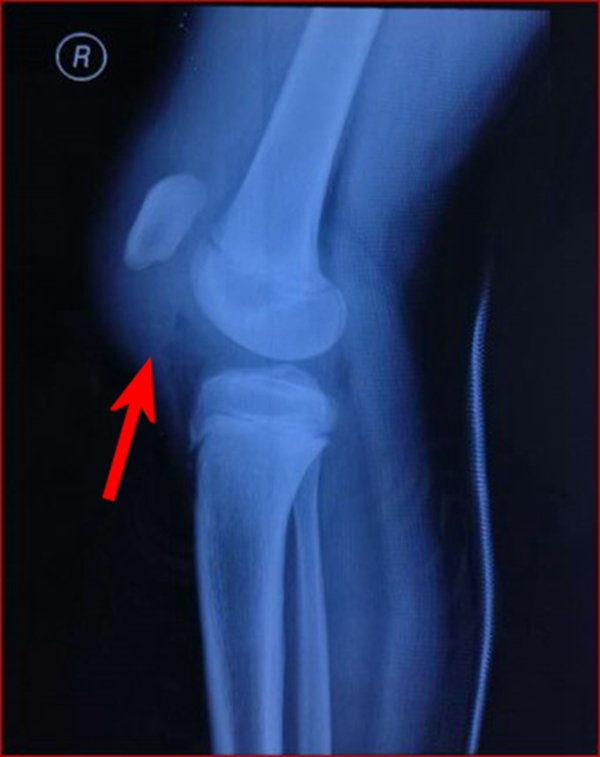

图4

在膝屈曲或半屈曲时,股四头肌剧烈抗阻力收缩应力作用于髌骨支点,演变成剪应力,致使髌骨软骨骨移行区分离剥脱,形成儿童特有的髌骨袖套状撕脱骨折。

影像学表现

1.髌骨上、下极的斑片、点状薄层骨组织影像或半环、新月形骨块阴影,同时还应注意髌骨有否高位、低位及髌韧带、股四头肌腱软组织影是否松弛。